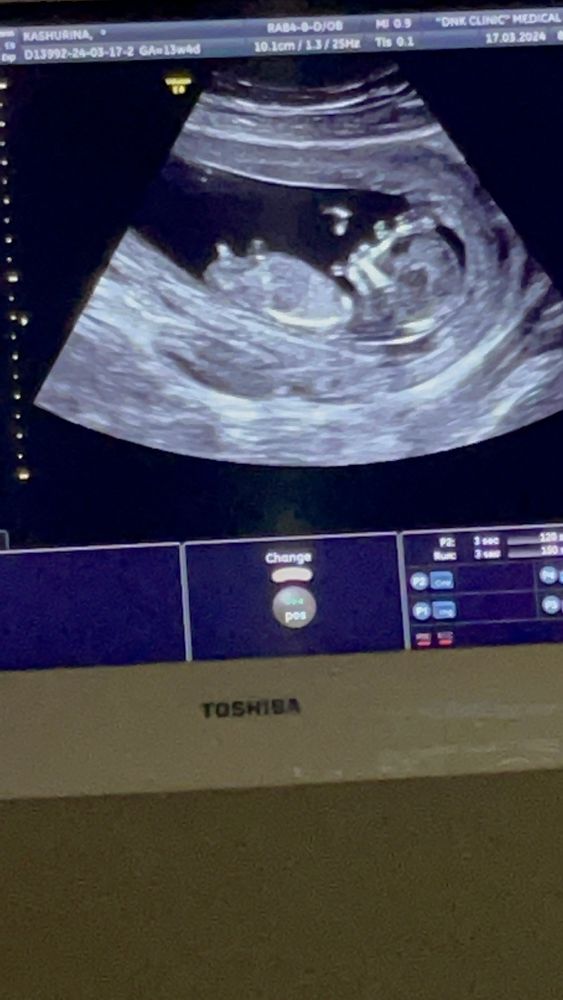

Девочка или мальчик ? 12 недель 5 дней

Анализы, скринингиПомогите 🤣 первый скрининг был сегодня )

врач молчаливая .. сначала сказала вроде девочка потом сказала на мальчика похоже и все 🤷🏼♀️

По первому фото девочка. На втором непонятно что это, на бугорок не очень похоже

Оооо:) на первом фото реально девочка, на втором 100% мальчик😁 как будто фотки двух разных пупсиков

Мальчик